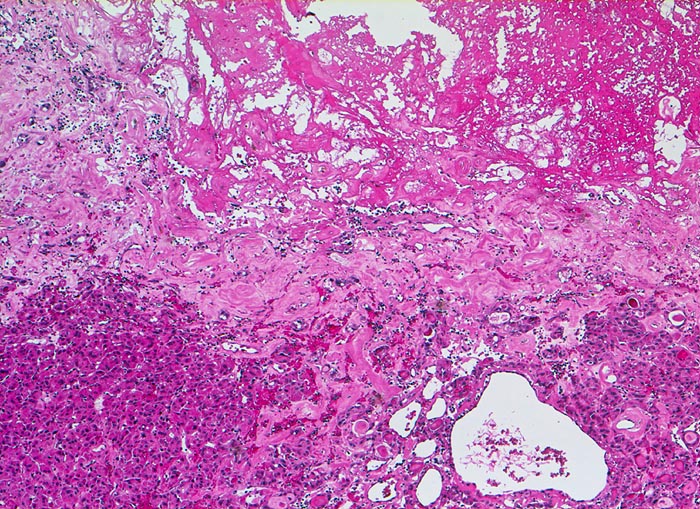

Entscheidend für die Diagnose eines follikulären Schilddrüsenkarzinoms in Abgrenzung zu einem gutartigen follikulären Schilddrüsenadenom ist der Nachweis eines Durchbruchs der Tumorkapsel (> 2753) (> 4951) und/oder ein Einbruch in Venen (> 4953) (> 8265) innerhalb oder jenseits der Tumorkapsel sowie das Fehlen morphologischer Kernmerkmale eines papillären Schilddrüsenkarzinoms. Zytologische Atypien kommen auch bei gutartigen follikulären Adenomen vor und sind deshalb kein Malignitätsmerkmal. Da Kapseldurchbrüche und Gefässeinbrüche nur am Gewebsschnitt diagnostiziert werden können, ist eine präoperative zytologische Diagnose eines follikulären Schilddrüsenkarzinoms anhand der Feinnadelpunktionszytologie nicht möglich.

• Kapseldurchbrüche: Die breite bindegewebige Kapsel wird an mehreren Stellen pilzförmig vorgewölbt und an einigen Orten vollständig durchbrochen.

• Keine eindeutigen Gefässeinbrüche (keine Tumorthromben oder endothelialisierte Tumorzapfen in Venen der Kapsel oder jenseits der Kapsel). Das sollte der Kliniker dem Pathologen mitteilen: